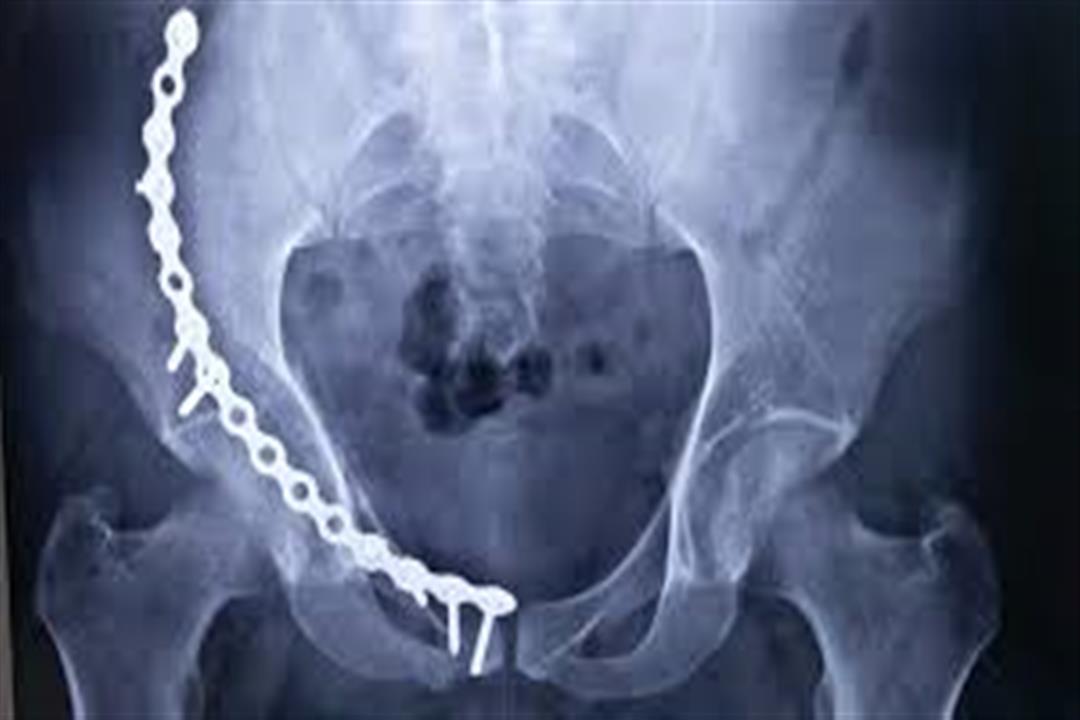

8 - كسر في الحوض

وقد يتسبب السقوط المفاجيء على المقعدة في حدوث كسر في الحوض يؤثر على الحركة، صعوبة التحكم في البراز، والبول، ويمتد الأمر إلى إصابة الشخص بالشلل.